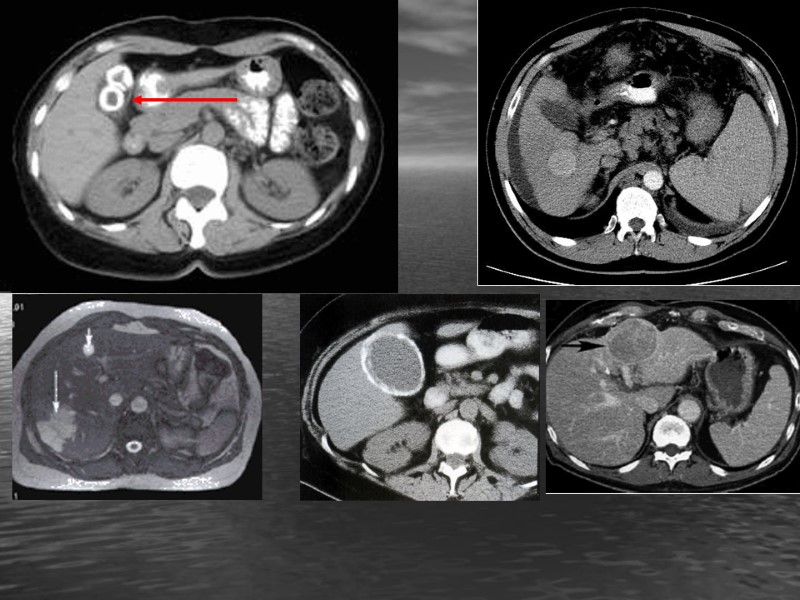

Методы лучевой диагностики ГБС. Ультрозвуковые методы исследования. Сонография Цветное допплеровское картирование Энергетическое картирование Импульсная допплерография Уз-ангиография 3Д виртуальная эхоангиография. УЗ- с е м и о т и к а. Форма, размеры, положение, контуры печени, желчного пузыря. Локализация участков поражения, их количество, эхогенность (изо-, гипо-, гипер, ан-, гетеро-), структура, форма, размеры, контуры, эффект дорожки (эхопозитивная, эхонегативная).

ВС- Анэхогенный участок в паренхиме МС – жидкостное образование (киста, абсцесс) Киста печени Абсцесс Многокамерная киста печени

ВС: Нарушение эхоархитектоники печени (гипер-, гипо-, гетеро- эхогенных участков в паренхиме). МС: опухоль, Метастазы, эхиноккоковая киста. Метастазы Гемангиомы Злокачественная опухоль Эхинококковая киста

ВС: Гиперэхогенный участок в паренхиме печени, полости желчного пузыря, протоков с эффектом эхонегативной дорожки. МС –Конкремент, обызвествление. . Конкремент ЖП и протоке Обызвествление в паренхиме Опухоль желчного пузыря

ВС: Утолщение стенок ЖП, протоков МС: Склерозрование, отек, опухоль Острый холецистит ВС: Изменение размеров и формы ЖП, протоков МС: Аномалии, воспаление, опухоль